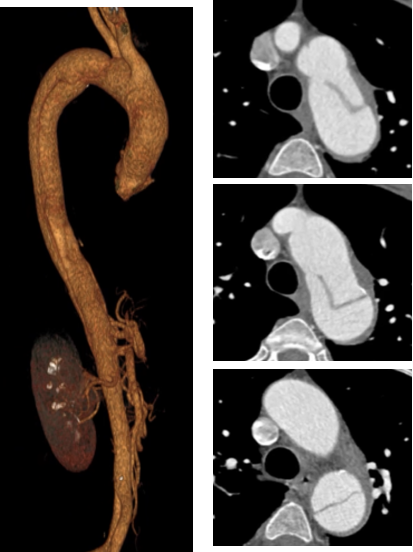

罕某,男,65岁,“发现主动脉弓部瘤5月”入院,主动脉CTA提示:主动脉弓部瘤。

术前CTA

术前造影

术后造影

手术用时 125 分钟